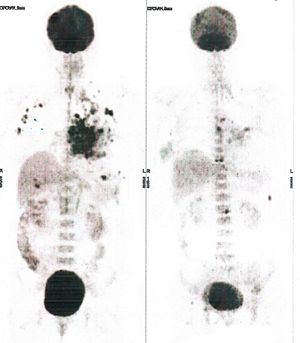

Below are some of the cases, from more than 80 cases we have treated so far with good results. When reading the PET/CT scans, the picture on the left is before treatment, and the picture on the right is after treatment. The intensity of black represents the activity of the cancer, but some black areas are not cancer: brain, heart, radioactive urine in bladder. For the heart, the intensity of black depends on the number of hours of fasting: if more than 10 hours, the heart is not even black, but if fasting is less than 6 hours, it is very black. The intensity of black in the brain can be variable in different scans depending on the brain activity at the time of the scan. The intensity of black in the radioactive urine can also be variable due to the hydration of patients and the time of injection of diuretic.

CASE NO: 2 (HEPATOCELLULAR CARCINOMA)

A 40+ man with hepatocellular carcinoma, an incurable cancer. After 2 treatment, the activity of the hepatocellular carcinoma is less.

CASE NO: 2 (HEPATOCELLULAR CARCINOMA) - After a few more treatments

After another few treatment, the activity of the hepatocellular carcinoma is much less. The patient never came back for further treatment, but this case, and case no: 1, shows that incurable hepatocellular carcinoma, often seen in hepatitis B and C patients, can be cured.